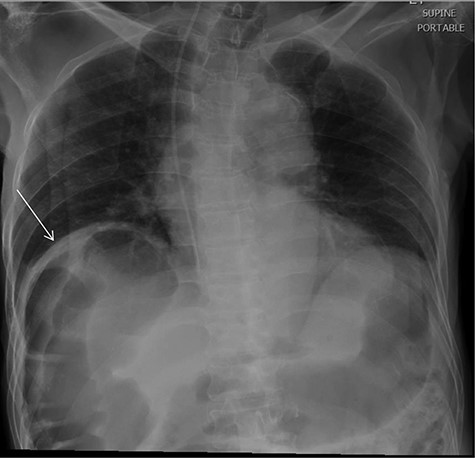

Chest X-Ray was unremarkable except for the visualized part of the abdomen that demonstrates distended bowel filled with gases (Fig. 1).

chest X-ray revealed visualized part of the abdomen demonstrate distended bowel filled with gases under the right hemidiaphragm.